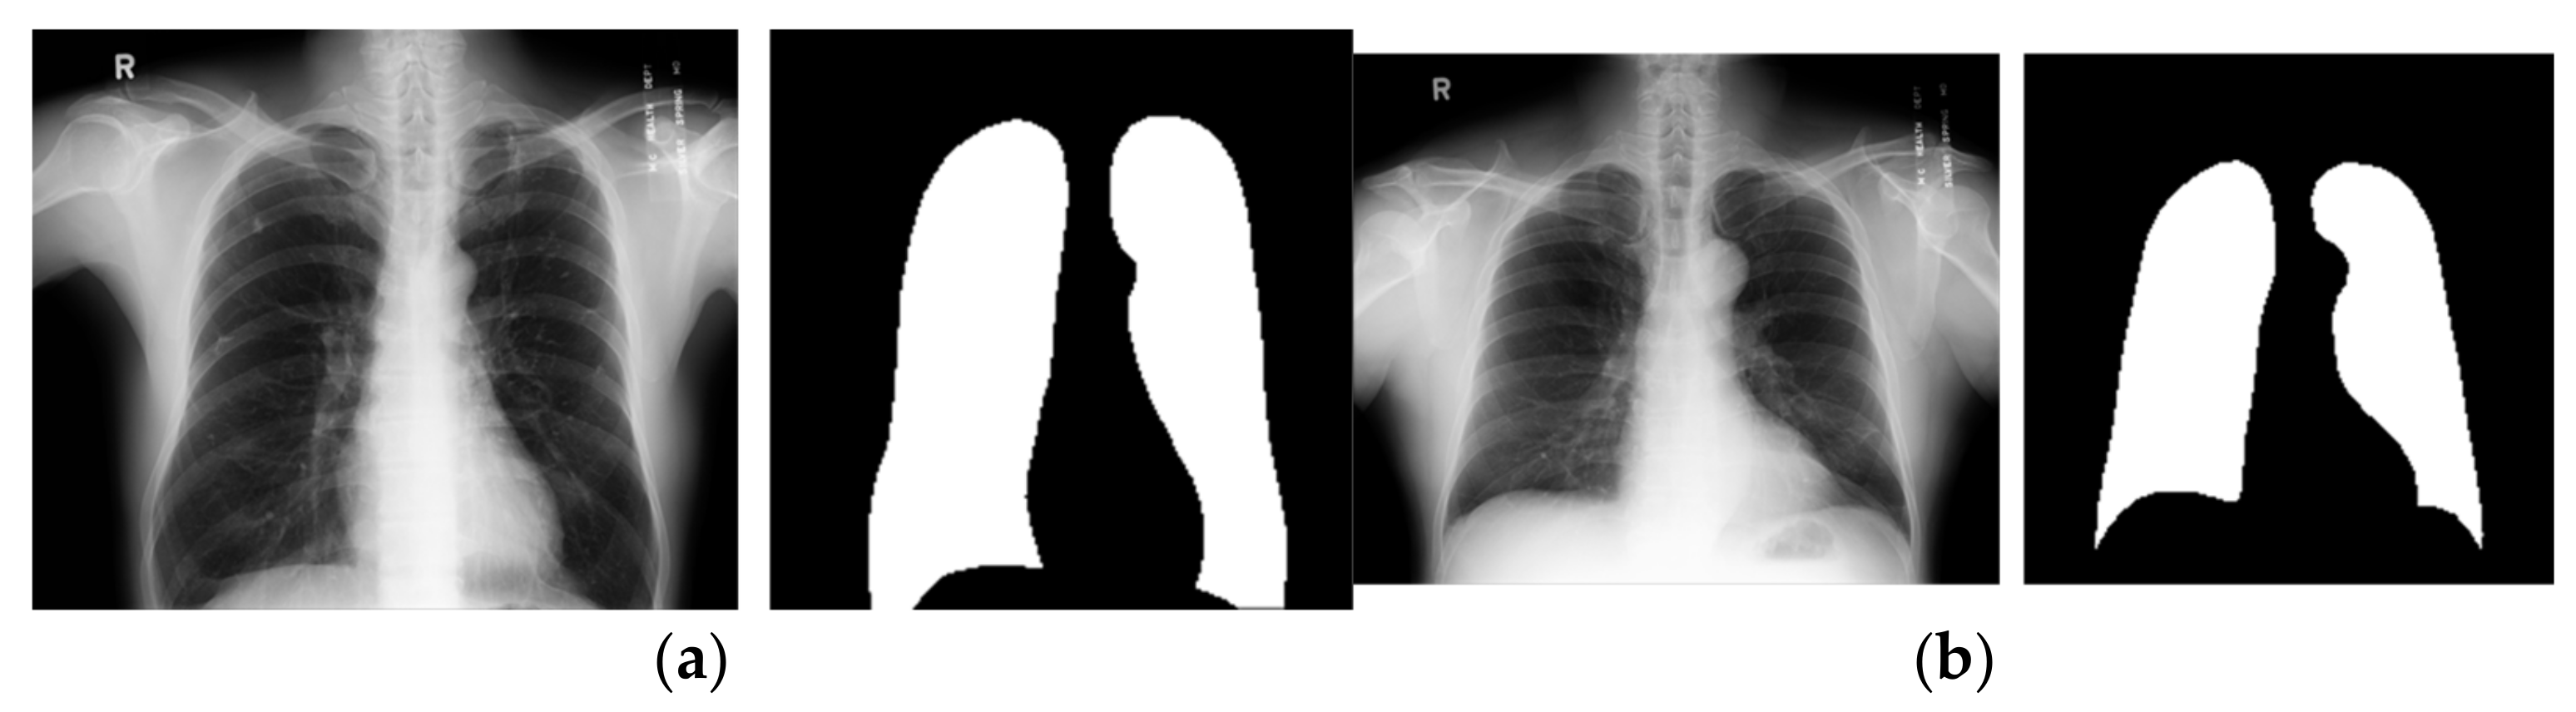

2.2.3. Shenzhen Hospital and Montgomery County Chest X-Ray Sets

The Shenzhen and Montgomery CXR sets consist of images obtained from their respective regions in China and the United States and are publicly accessible. While these datasets are primarily used for classification tasks, their application has been extended to include lung segmentation tasks [27,28].

The Shenzhen dataset contains 662 CXR images with a resolution of approximately 3000 × 3000 pixels. Unlike the previously mentioned datasets, the Shenzhen dataset does not include corresponding ground truth masks. Instead, segmented masks created by students and teachers from the Department of Computer Engineering at the National Technical University of Ukraine were utilized as ground truth masks [27,28,35]. However, since 96 out of the 662 images lack segmentation masks, this study used only the remaining 566 images with available masks. On the other hand, Montgomery’s dataset included 138 CXR images with their ground truth masks. Image size varied from 1255 × 989 to 3001 × 3001 pixels. In this paper, we adopted the widely used methodology from the literature, in which the first dataset was utilized for training, and the second dataset was employed for testing the models [27,28,35]. Figure 7 presents representative examples of each dataset.

Figure 7. Images from (a) Shenzhen Hospital CXR Set; (b) Montgomery County CXR Set.